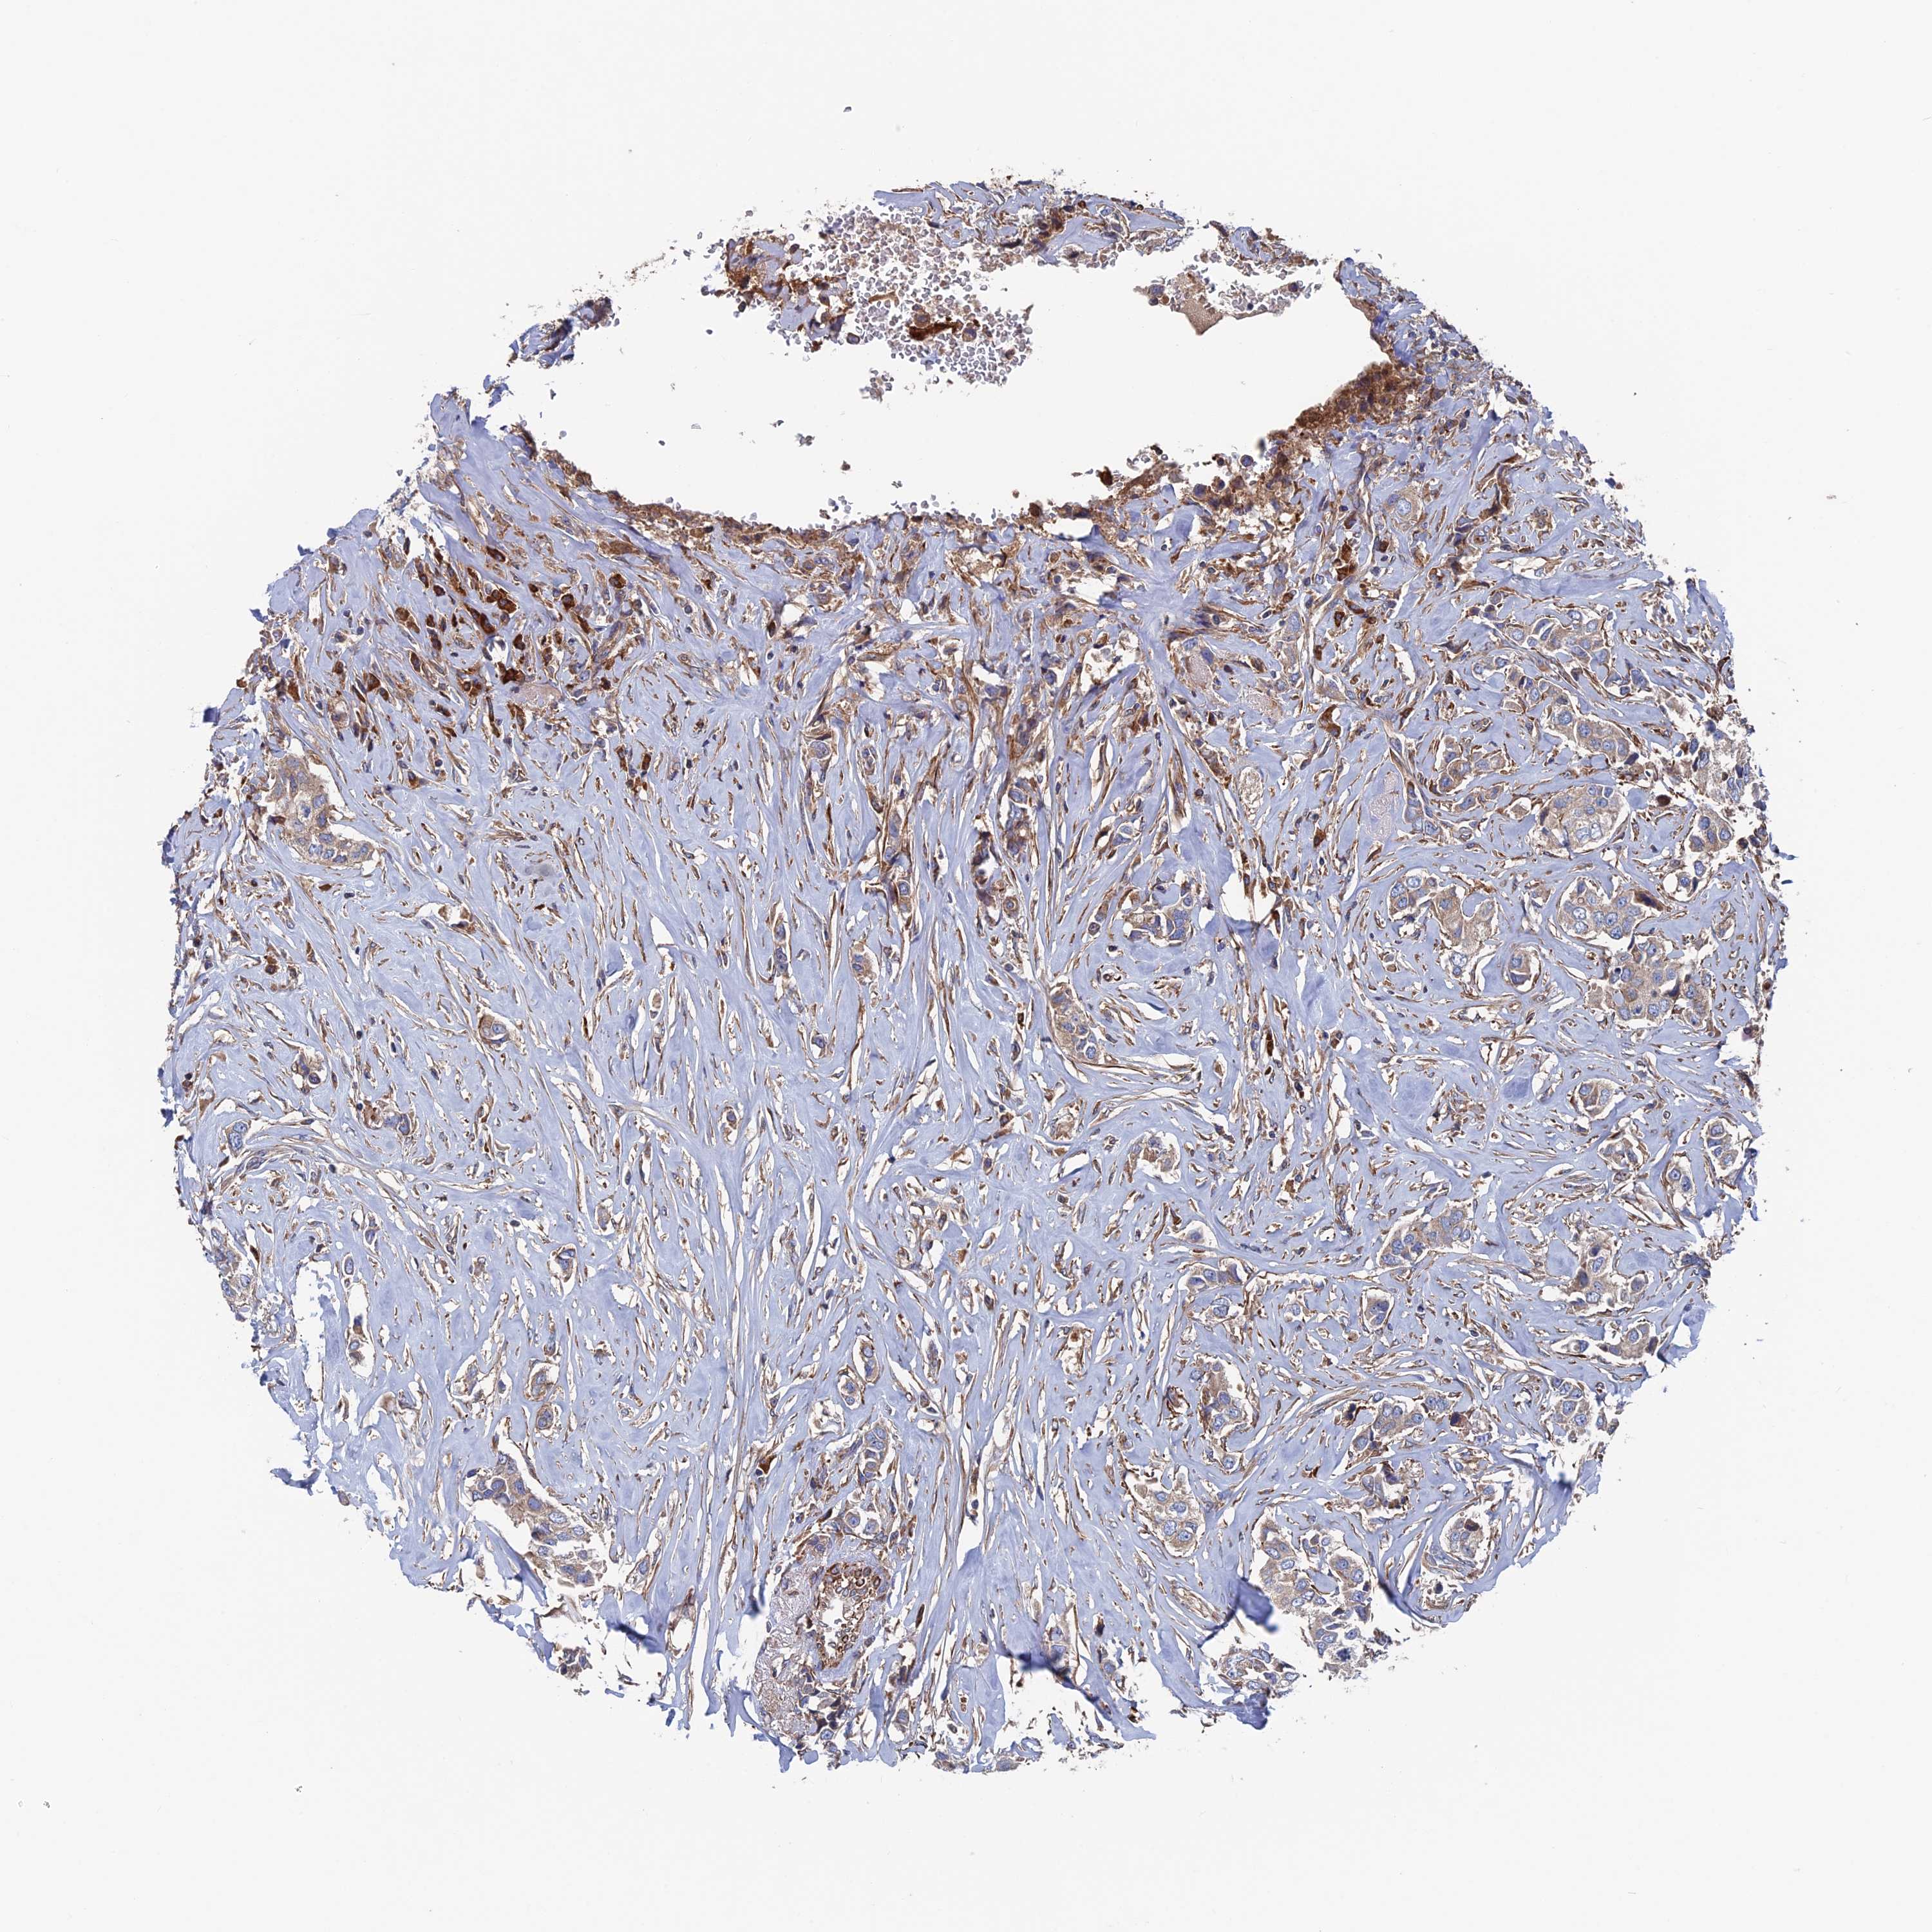

CANCER BREAST CANCER Show tissue menu

BRCA TCGA BRCA VALIDATION PROTEIN EXPRESSION